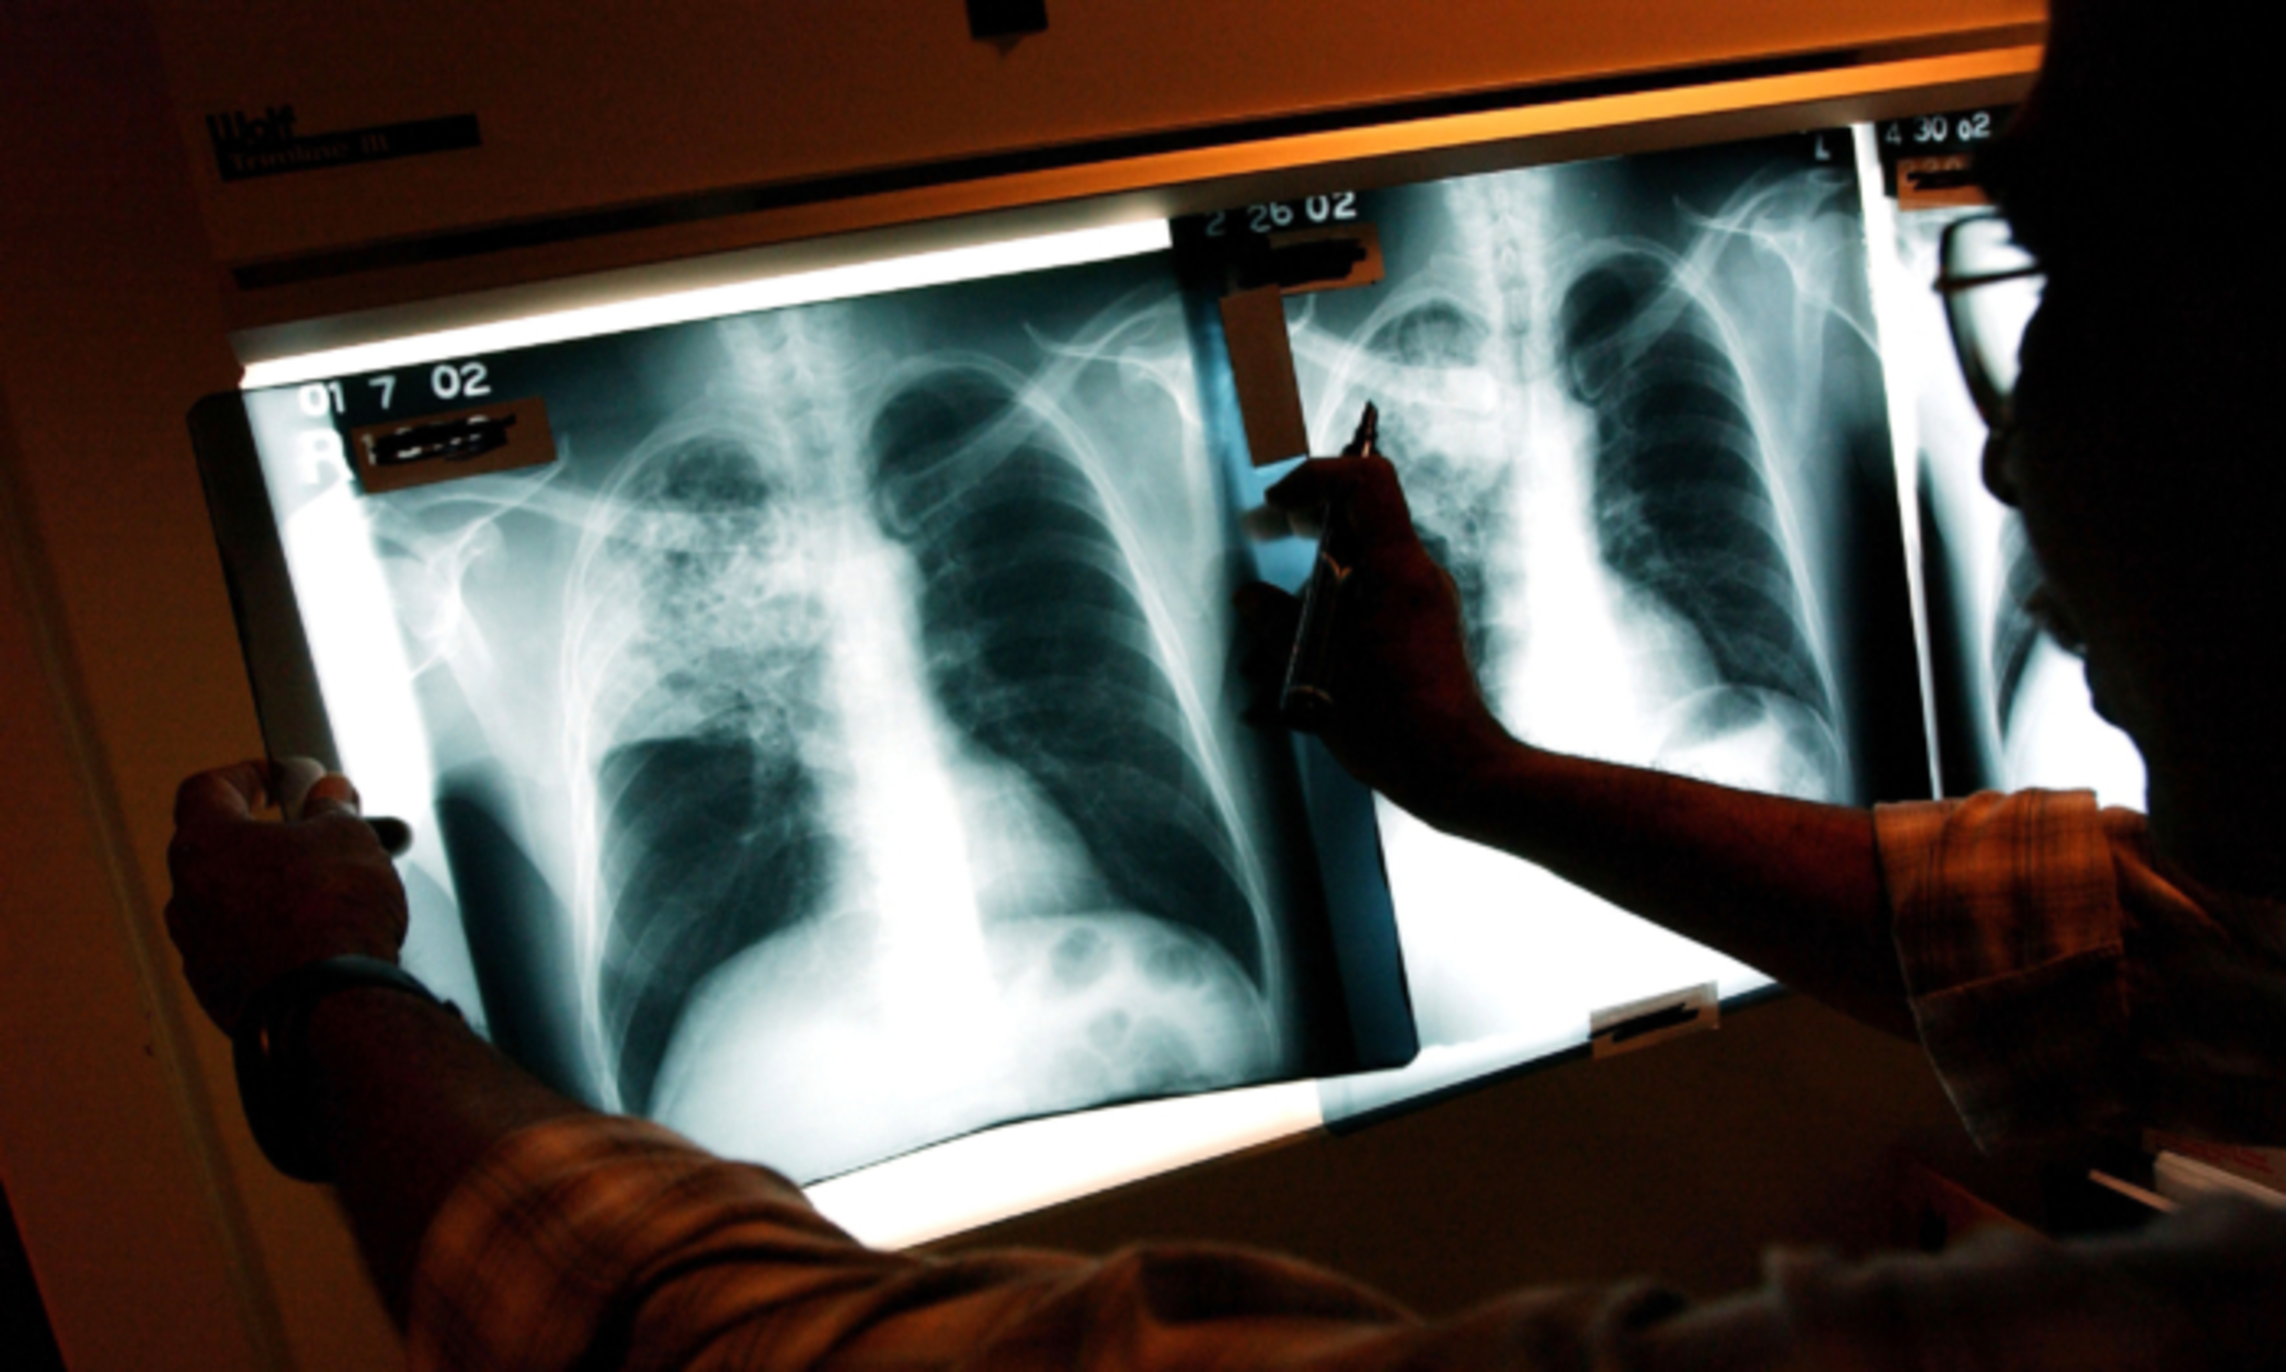

Emergency Declared on Tuberculosis in California City: What to Look For

Authorities in a California declared a health emergency last week due to an outbreak of tuberculosis in Long Beach after it left at least one dead and more than a dozen infected. The Long Beach city health officer issued the declaration on May 2 to increase resources for tracking, screening and treating people who have been exposed in the outbreak linked to a hotel, the city health department said in a news release. As of April 29, there were 14 cases. One person has died, nine have been hospitalized at some point and about 170 people have been identified as likely to have been exposed....